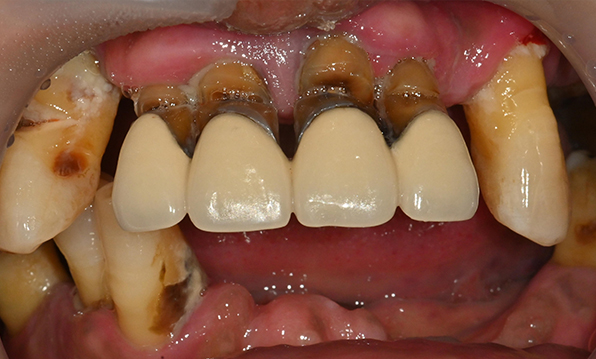

Case 01

Before After